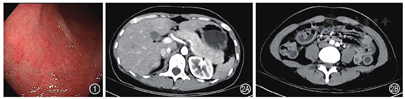

结肠镜检查:横结肠至直肠黏膜呈颗粒状、血管纹理不清、散在糜烂,Mayo内镜评分为2分,见图1。活检组织病理:直肠黏膜慢性炎症伴糜烂,可见隐窝炎。全腹部CT:胰腺形态饱满;部分结肠及直肠管壁稍增厚水肿,并少许渗出,见图2。心脏彩超:少量心包积液。磁共振胰胆管造影(magnetic resonance cholangiopancreatography,MRCP):胰腺周围少量渗出,肝内外胆管未见明显扩张及充盈缺损。